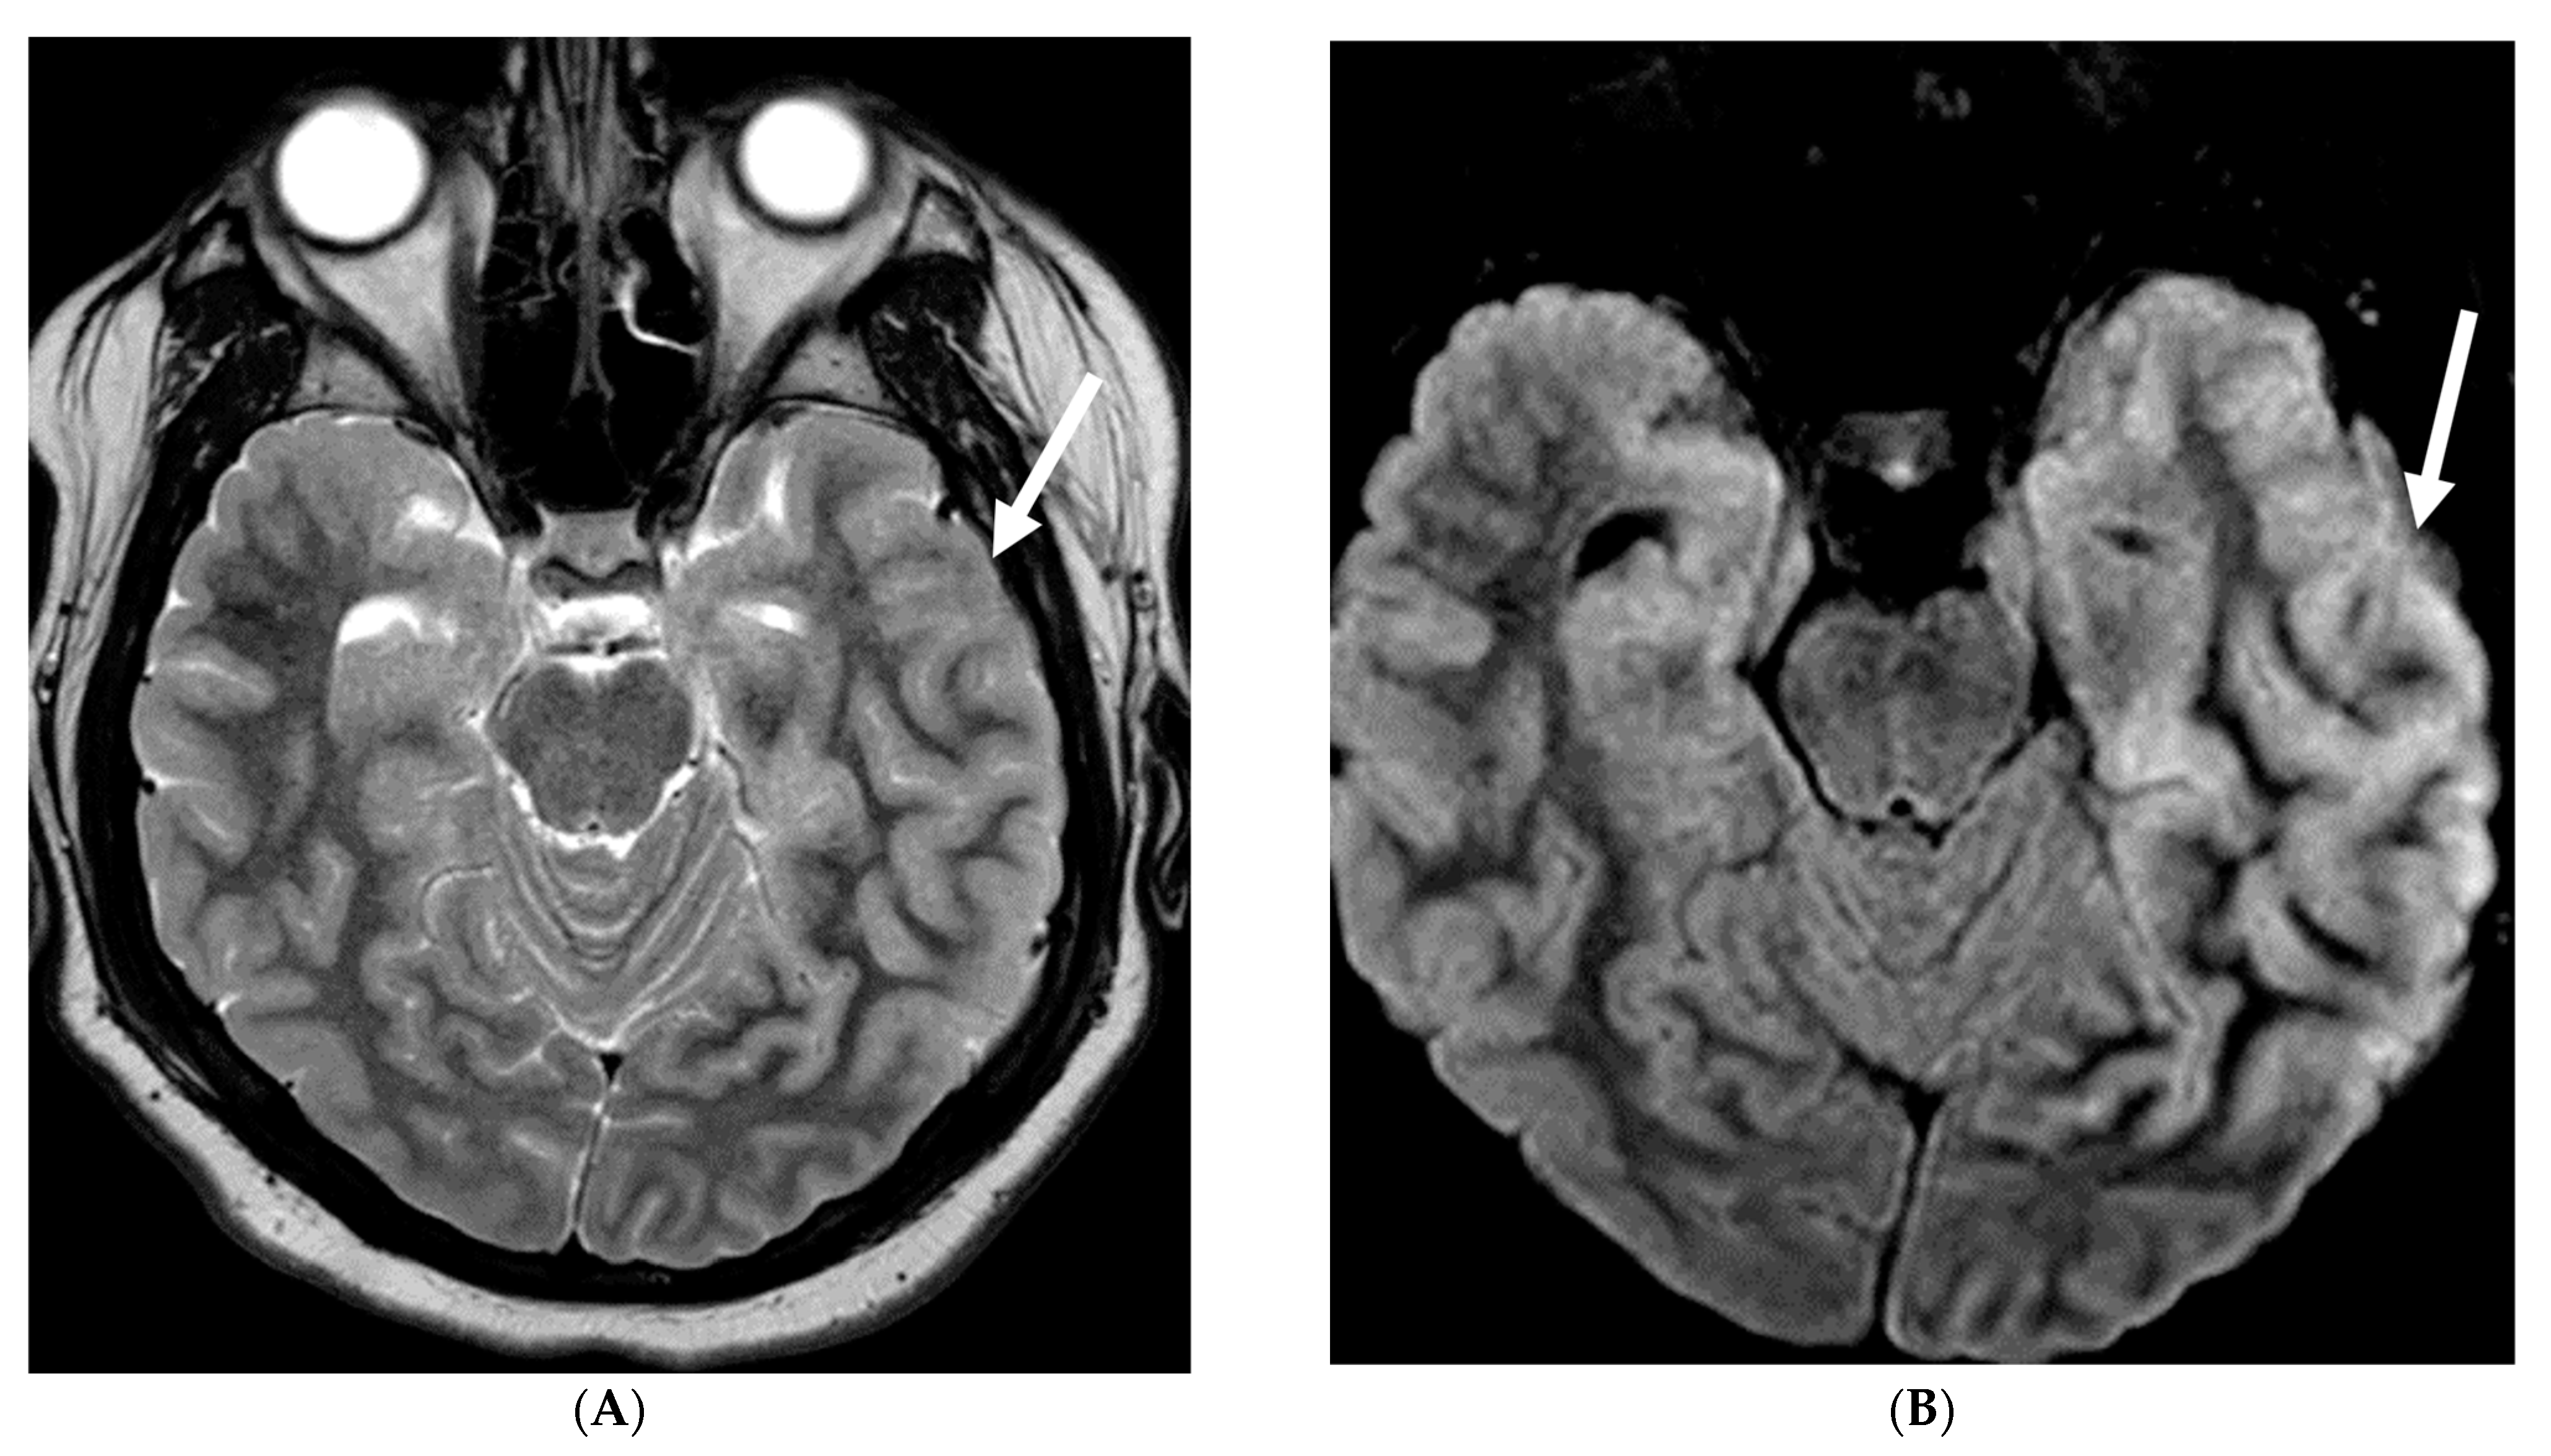

Imaging findings in GPA include chronic hypertrophic pachymeningitis (most common) representing granulomatous involvement. This can be diffuse or focal, with the latter showing dural thickening and enhancement adjacent to a sinus or orbit [113]. Tentorium involvement is common, presenting as the ‘Eiffel by night’ sign [114]. Cerebral vasculitis appears as multiple T2 hyperintense white matter lesions potentially showing diffusion restriction and patchy enhancement. Cerebral atrophy may be observed, attributed to steroid treatment and/or vasculitis. Pituitary involvement can range from normal to enlarged gland size, with thickened stalk and peripheral enhancement. Cranial nerve involvement, particularly of the olfactory and optic nerves, is common due to mass effect from adjacent lesions or hypertrophic pachymeningitis (Figure 22) [112].

Figure 22.

Post contrast axial FLAIR (A), axial T1 FS (B), sagittal T1 Right (C) and Left (D): 10-year-old girl with elevated ANCA, headache and mild LUE weakness. There is bilateral anterior temporal smooth dural enhancement (white arrows). Diagnosis: Antineutrophilic cytoplasmic antibody (ANCA) associated vasculitis, likely granulomatosis with polyangiitis.